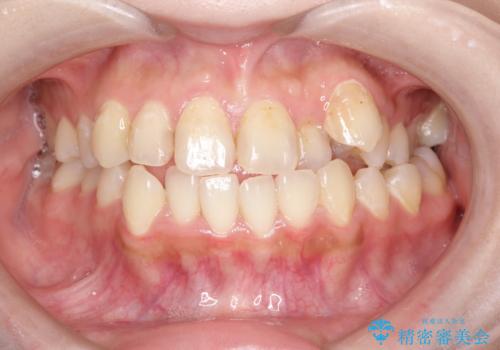

矯正をすれば口元もきれいになる という都市伝説のようなものがありますが、実際には大きな誤解だといえます。

口元は前歯による裏打ち以上に、口元を構成する筋肉・脂肪組織などによる影響を強く受けます。抜歯矯正ですらダイナミックな口元の変化が得られないこともあるのです。

口元と非抜歯矯正

したがって、非抜歯矯正では特殊な例を除いて「ほぼ口元は変わらない」事をよくご理解していただく必要があります。

加齢変化により口元の脂肪組織が減少することや、民族的素質としての顔面骨の形態的特性を無視しないという意味においても、無暗に抜歯をして前歯を下げることが得策ではないのは自明の事実といえます。